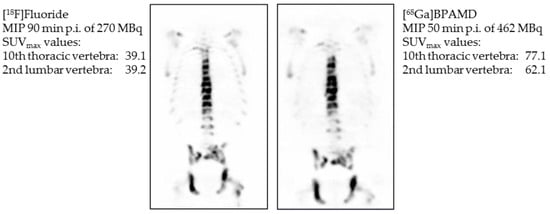

- Fellner, M.; Biesalski, B.; Bausbacher, N.; Kubícek, V.; Hermann, P.; Rösch, F.; Thews, O. 68Ga-BPAMD: PET-imaging of bone metastases with a generator based positron emitter. Nucl. Med. Biol. 2012, 39, 993–999. [Google Scholar] [CrossRef]

- Fellner, M.; Baum, R.P.; Kubíček, V.; Hermann, P.; Lukeš, I.; Prasad, V.; Rösch, F. PET/CT imaging of osteoblastic bone metastases with 68Ga-bisphosphonates: First human study. Eur. J. Nucl. Med. Mol. Imaging 2010, 37, 834. [Google Scholar] [CrossRef]

- Rösch, F.; Baum, R.P. Generator-based PET radiopharmaceuticals for molecular imaging of tumours: On the way to Theranostics. Dalton Trans. 2011, 40, 6104–6111. [Google Scholar] [CrossRef] [PubMed]